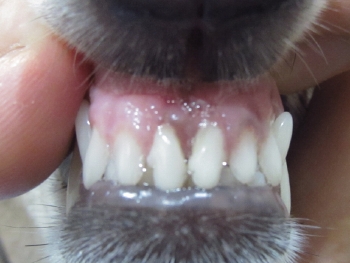

歯石除去 例1